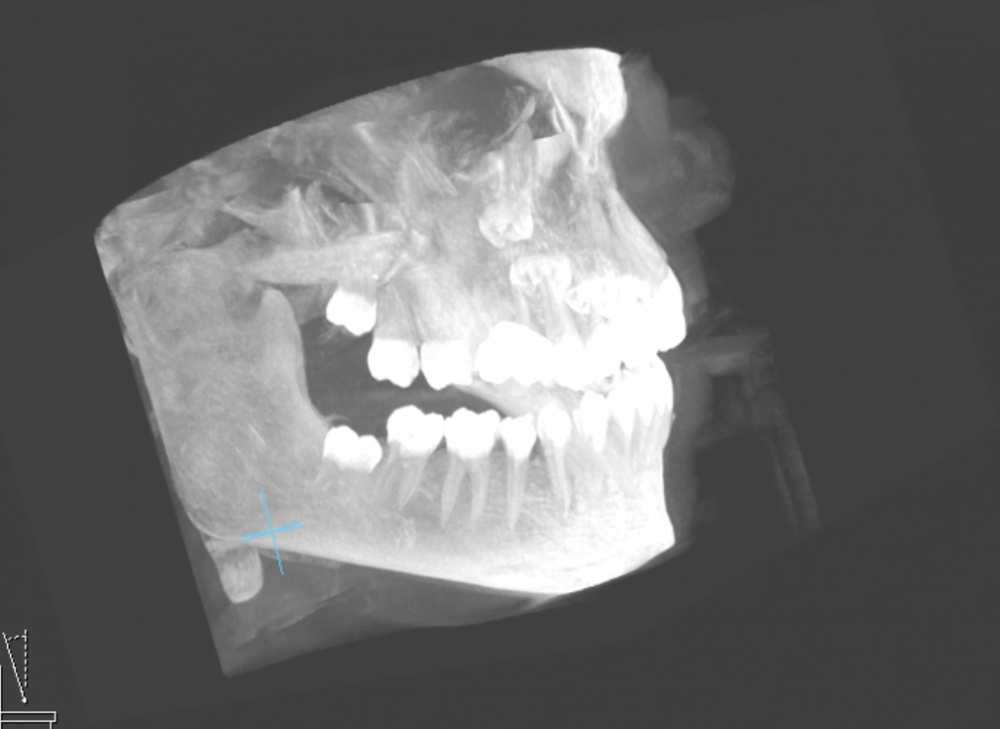

Faggott Опубликовано 3 мая, 2022 Автор Поделиться Опубликовано 3 мая, 2022 01.05.2022 в 21:50, Irouil сказал: Покажите КТ @Irouil, ссылка на DICOM-файлы из КТ: https://drive.google.com/file/d/1zzESnhJBWdFfQzYsPNaK6rfdAGsnEAcu/view?usp=sharing А это скрины 8-к (хотя я не уверена, что это нужные скрины) //было бы так хорошо, если бы мне кто-то раньше сказал, что КТ бесплатно высылают на почту (и высылают образ диска с программами и файлами, а не "файлы, которые вы сами открыть не сможете") и что на факультете, где есть ЭВМ и древние компы с линуксом, нет компов с дисководами //зато теперь у меня есть диск, который мне, к сожалению, некуда вставлять Ссылка на комментарий

Faggott Опубликовано 2 июля, 2022 Автор Поделиться Опубликовано 2 июля, 2022 Сегодня мне удалили 8-ки. На это ушло 40 минут, примерно 10 (у меня сбито ощущение времени без часов, так что это очень приблизительный срок) из которых мы ждали действия анестезии. Анестезия уже отошла, и с языком всё просто прекрасно. Как и с остальными частями лица. Даже ничего не болит (из-за пакетика Нимесила, возможно). //а ещё мне дали классный кусок льда в синей грелке. не знаю, сильно ли это поможет, но я прикладываю его на 15 минут с промежутком в час. очень увлекательное занятие Вот и они: 3 Ссылка на комментарий